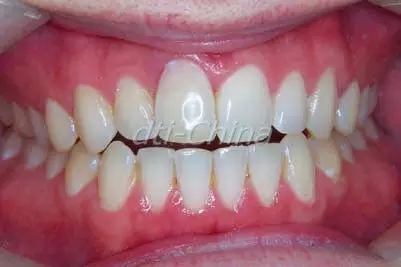

患者是一個30歲健康男性, 來診所檢查失去功能的上頜右中切牙, 過去在1993年的一次足球意外中因臉部受到肘擊導致上頜右中切牙的外傷,在事故大約一周之后, 對患者的牙齒進行了根管治療,最后牙齒開始變色而且越來越不整齊(圖1)。影像檢查發(fā)現(xiàn)內(nèi)吸收。通過臨床診斷,發(fā)現(xiàn)所有其它的上下前牙都完好無損,牙周檢查顯示健康的牙齦組織,患者擔心他的前牙會意外斷裂, 并希望立即替換患牙。

患者戴著愈合基臺再次來到我們診所,取出愈合基臺,立即放置一個諾貝爾種植系統(tǒng)臨時基臺并制作一個臨時義齒。關注臨時義齒的輪廓是對牙齦結(jié)構的最好支持。使用碳化鎢鉆讓即刻暫時基臺的塑料基底冠變粗糙,以此來增強完整臨時性材料的依附性。拋光后的臨時義齒置于即刻暫時基臺上,使用小劑量的流動樹脂來增強牢靠度,臨時冠已經(jīng)制作完成,并且完全沒有咬合和功能性,確保種植體有足夠的骨結(jié)合時間而不必被咬合力量干擾,在6個月的治愈過程中定期性的進行臨時修復查看 牙齦的適應情況(圖2)。